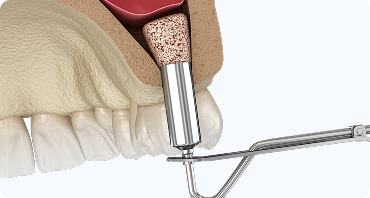

상악동 거상술

윗니 잇몸뼈의 두께가 얇을 경우, 상악동 막을 정교하게 거상하여

인공뼈를 보강하는 전문 시술입니다.

임플란트 식립을 위한

뼈 높이를 확보하여 장기적인 성공률을 높입니다.